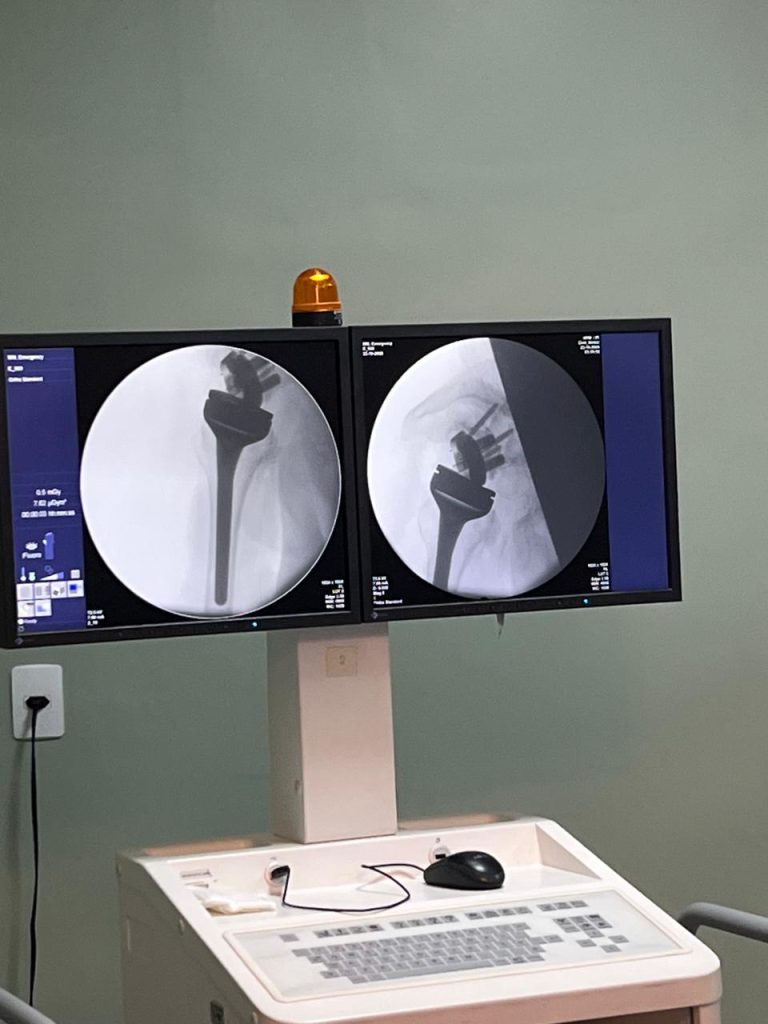

A Secretaria de Estado da Saúde do Piauí (Sesapi), por meio do Hospital da Polícia Militar (HPM), realizou na quarta-feira (22) sua primeira cirurgia de prótese de ombro reversa. O procedimento, considerado inédito no Piauí na rede pública estadual, marca um importante avanço na oferta de cirurgias ortopédicas de alta complexidade e amplia as possibilidades de reabilitação de pacientes com graves lesões no ombro.

A cirurgia de prótese reversa é indicada para casos de ruptura irreparável do manguito rotador, artrose avançada ou fraturas complexas da articulação. Diferente da prótese convencional, o modelo reverso inverte a posição anatômica das partes da articulação — a esfera metálica é fixada na escápula e o soquete no úmero — permitindo que o músculo deltoide substitua a função dos tendões lesionados. Essa inovação devolve a mobilidade ao ombro e possibilita que o paciente realize novamente atividades simples do dia a dia.